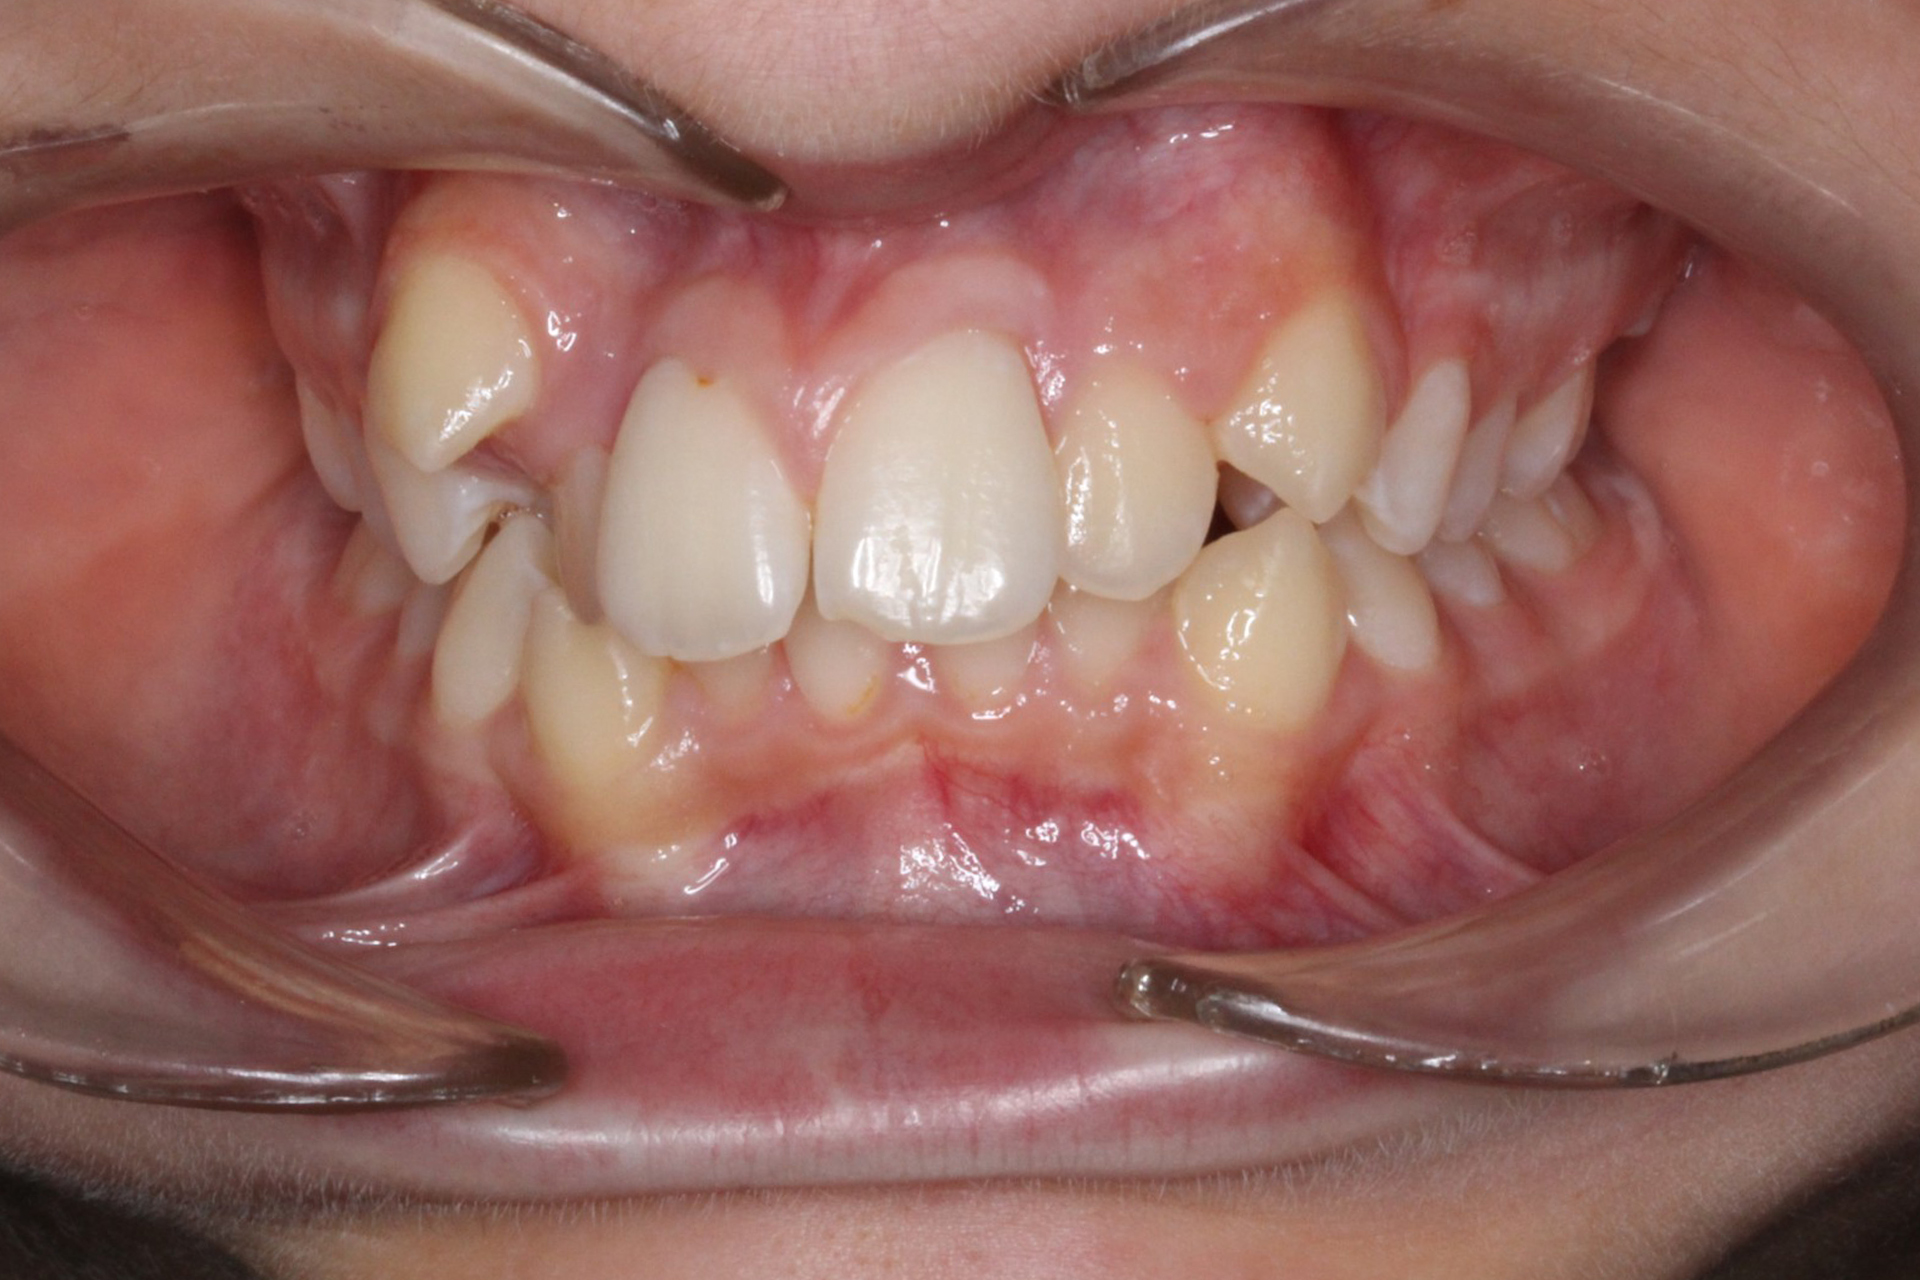

Se observa una maloclusión con apiñamiento dental anterior y posterior, acompañada de asimetria en la disposición de las arcadas. La relación molar corresponde a una clase II bilateral, lo que afecta la oclusión global. El plan de tratamiento se orienta a mejorar alineacion y nivelacion de los dientes sin extracciones, buscando optimizar el espacio disponible. Este enfoque permite además favorecer higiene у funcion, reduciendo el riesgo de problemas periodontales у mejorando la estética у la mordida del paciente.